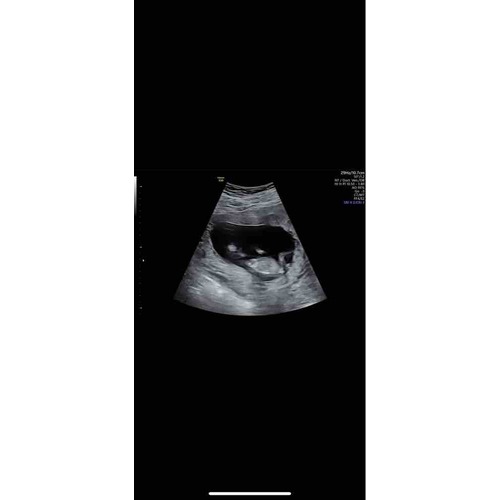

Ik heb deze foto.

Een meisje?🤩

Ik hoopte op een zijprofiel 😊 Hier is het helaas niet te zien

Verder heb ik alleen deze waar meer opstaat

Had je niet gelijk deze kunnen plaatsen 😬😬😬 Ik denk 💗